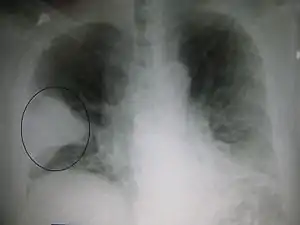

Chest film showing increased opacity in both lungs, indicative of pneumonia